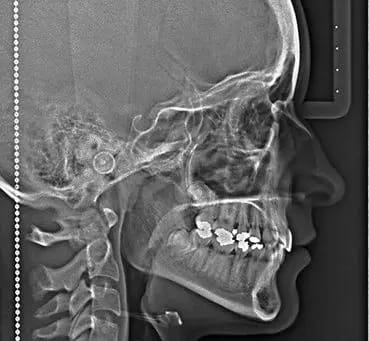

En Estudio Rx, ofrecemos el servicio de Radiografía Lateral de Cráneo, un estudio radiológico esencial en la evaluación de la estructura ósea y las relaciones anatómicas del cráneo y la mandíbula. Esta radiografía proporciona una imagen lateral del cráneo, permitiendo a los especialistas analizar con precisión las proporciones y alineaciones de los huesos faciales y dentales.

La Radiografía Lateral de Cráneo es fundamental en el diagnóstico y planificación de tratamientos de ortodoncia, cirugía maxilofacial, y en el seguimiento de problemas de crecimiento y desarrollo craneofacial. Esta técnica permite evaluar la posición de los dientes, la relación entre el maxilar y la mandíbula, y la estructura ósea del cráneo, proporcionando una visión completa que facilita un diagnóstico preciso y un tratamiento personalizado.